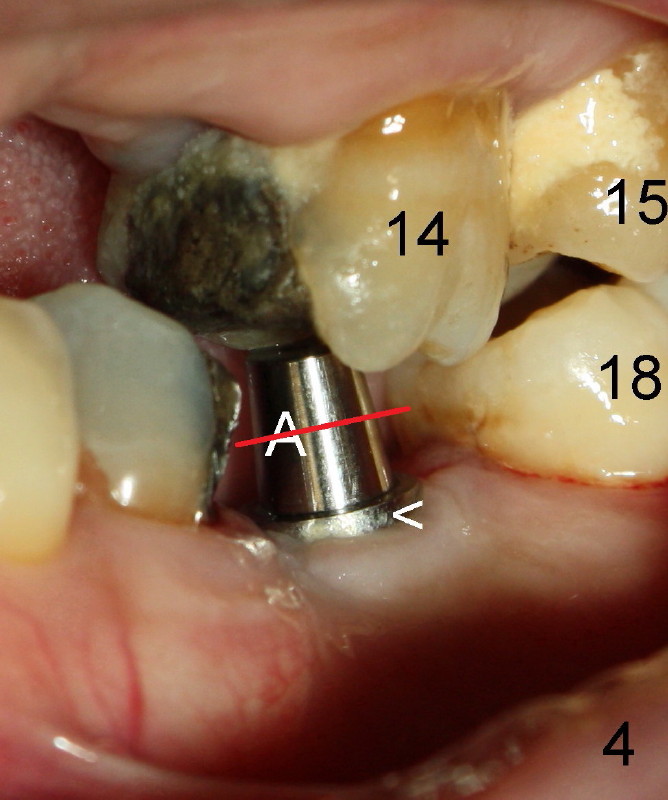

The teeth #15 and 18 cannot occlude when 4.5x5 mm abutment (Fig.4: A) is placed at #19 implant (<). It takes a while to trim the unipost from the top gradually in order to let #15 and 18 have normal occlusal contact (Fig.5 mirror image). By that time, the abutment is approximately 2.5 mm tall.

It has never occurred to me that the abutment can be truncated with a fissure bur. How can we avoid cutting the abutment (Fig.4 red line) too short? Retention of crown may be affected if the abutment is too short.